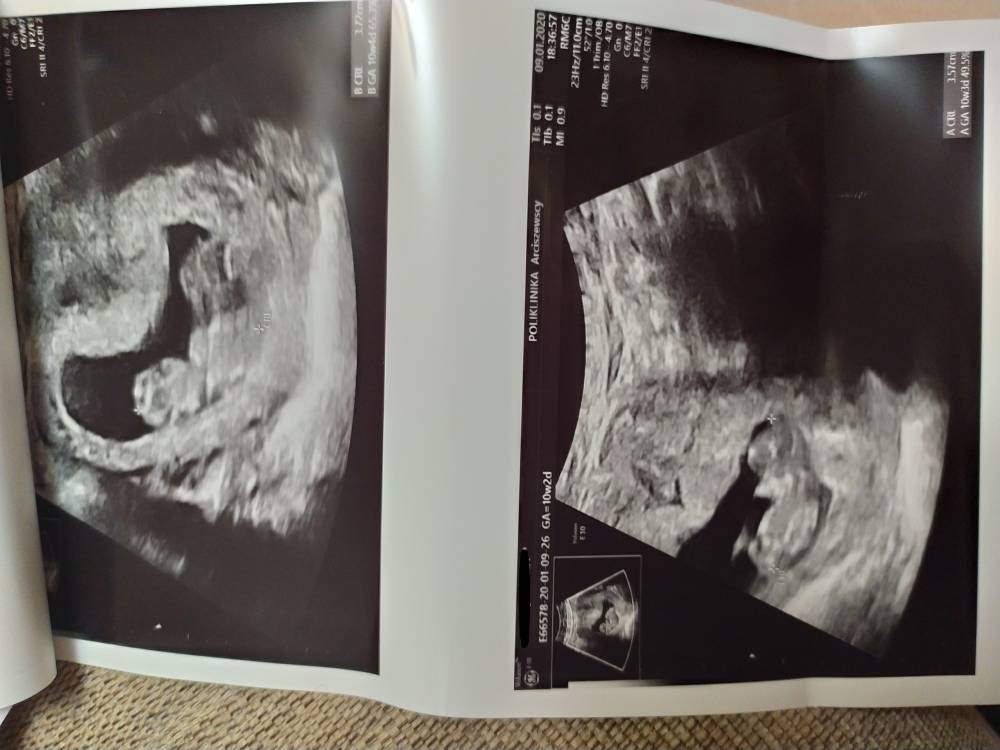

Wczoraj byłam na wizycie, dzieciaczki wyglądają na zdrowe, mają po ok. 3,5cm [emoji3059]tylko są położone bardzo blisko siebie i to mnie martwi [emoji20]. Na 30.01 jestem umówiona na prenatalne. Nadal nie mam lekarza prowadzącego, bo wizytę w poradni mam dopiero na marzec (co jest jakąś kpiną). Wczoraj lekarz mi powiedział, że od 26 tygodnia będę musiała już leżeć w szpitalu i rozwiązanie w 33 tygodniu. Strasznie wcześnie [emoji43]

Wczoraj byłam na wizycie, dzieciaczki wyglądają na zdrowe, mają po ok. 3,5cm [emoji3059]tylko są położone bardzo blisko siebie i to mnie martwi [emoji20]. Na 30.01 jestem umówiona na prenatalne. Nadal nie mam lekarza prowadzącego, bo wizytę w poradni mam dopiero na marzec (co jest jakąś kpiną). Wczoraj lekarz mi powiedział, że od 26 tygodnia będę musiała już leżeć w szpitalu i rozwiązanie w 33 tygodniu. Strasznie wcześnie [emoji43]Zobacz załącznik 1066656